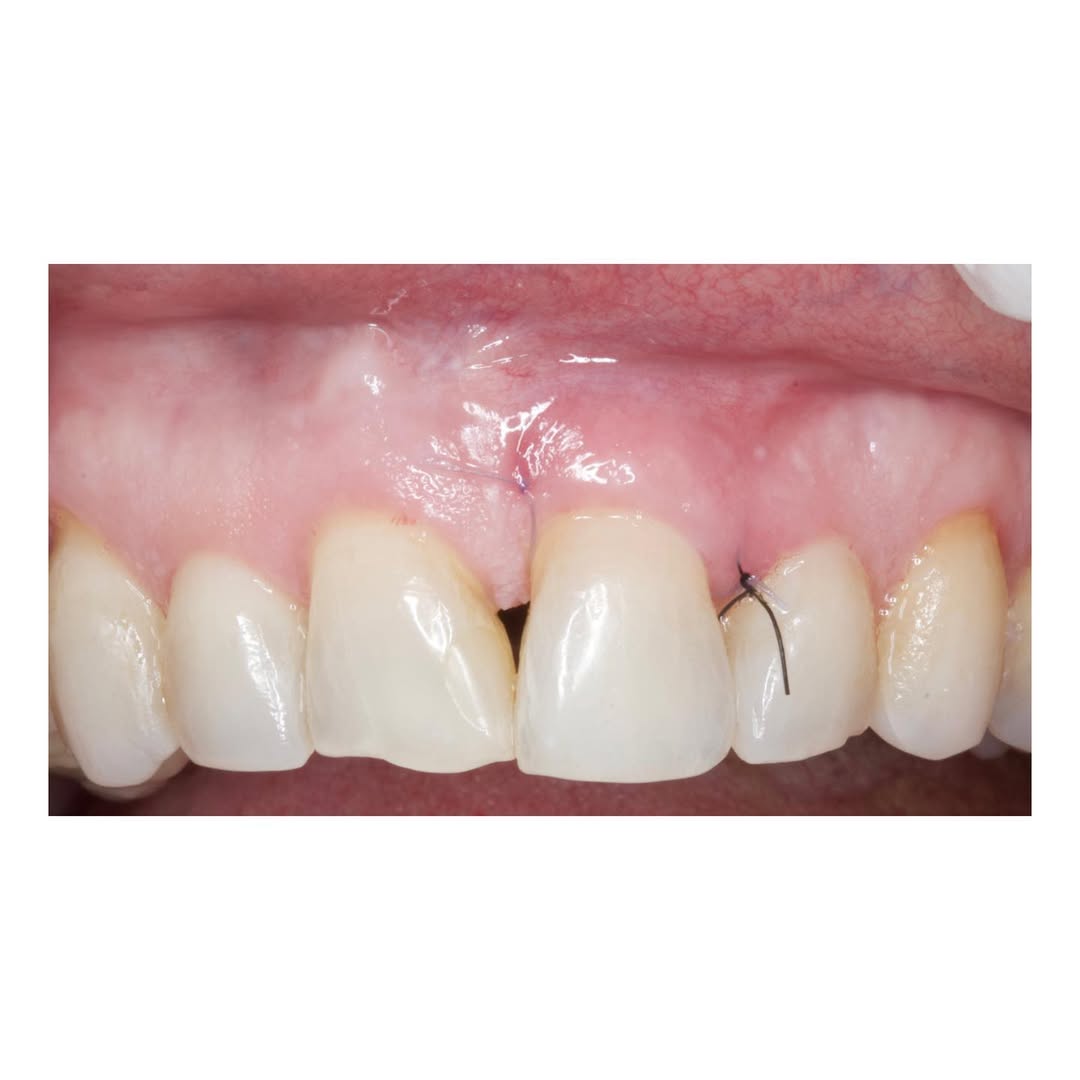

Durante una mañana, asistirás a una Cirugía Mucogingival de recubrimiento radicular de una recesión unitaria en 31 con frenillo asociado. Gracias al uso del microscopio y a la proyección en tiempo real en pantalla, verás exactamente lo mismo que veo yo durante la cirugía, sin tener que estar

Una estancia clínica pensada para quienes quieran iniciarse o dar un paso más en el campo de la cirugía mucogingival. Durante esta experiencia tendrás la oportunidad de aprender en directo cómo se planifica y se lleva a cabo una cirugía mucogingival mediante técnica de Túnel.

La sesión

Una estancia clínica pensada para quienes quieran iniciarse o dar un paso más en el campo de la cirugía mucogingival. Durante esta experiencia tendrás la oportunidad de aprender en directo cómo se planifica y se lleva a cabo una cirugía mucogingival